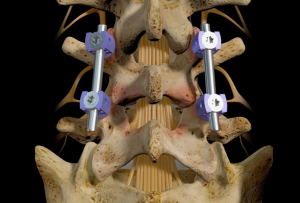

В зависимости от уровня фиксации мы разделили больных на 4 группы: больным I группы произведена фиксация двух сегментов, винты вводились в L4, L5 и S1 позвонки (рис. 1); в остальных группах производилась фиксация трех сегментов, при этом во II группе винты вводились в L3, L4, L5 и S1 позвонки, в III - в L3, L5 и S1 позвонки и в IV группе в L3, L4 и S1 позвонки (рис. 2).

Всем пациентам с I-II степенями смещения, за исключением одного, производилась фиксация двух сегментов - Ц_5 и L5-S1, т. е. они относились к I группе фиксации. У всех пациентов со спондилолистезом I степени и у двух II степени во время операции было достигнуто полное вправление смещенного позвонка. У остальных пациентов со II степенью смещения осуществлено вправление на 65 %. Угол смещения позвонка (по Митбрейту) уменьшился на 18,1 % от исходной величины. Угол сагиттальной ротации позвонка L5 и величина лордоза в данной группе, кроме одного случая, не изменились.